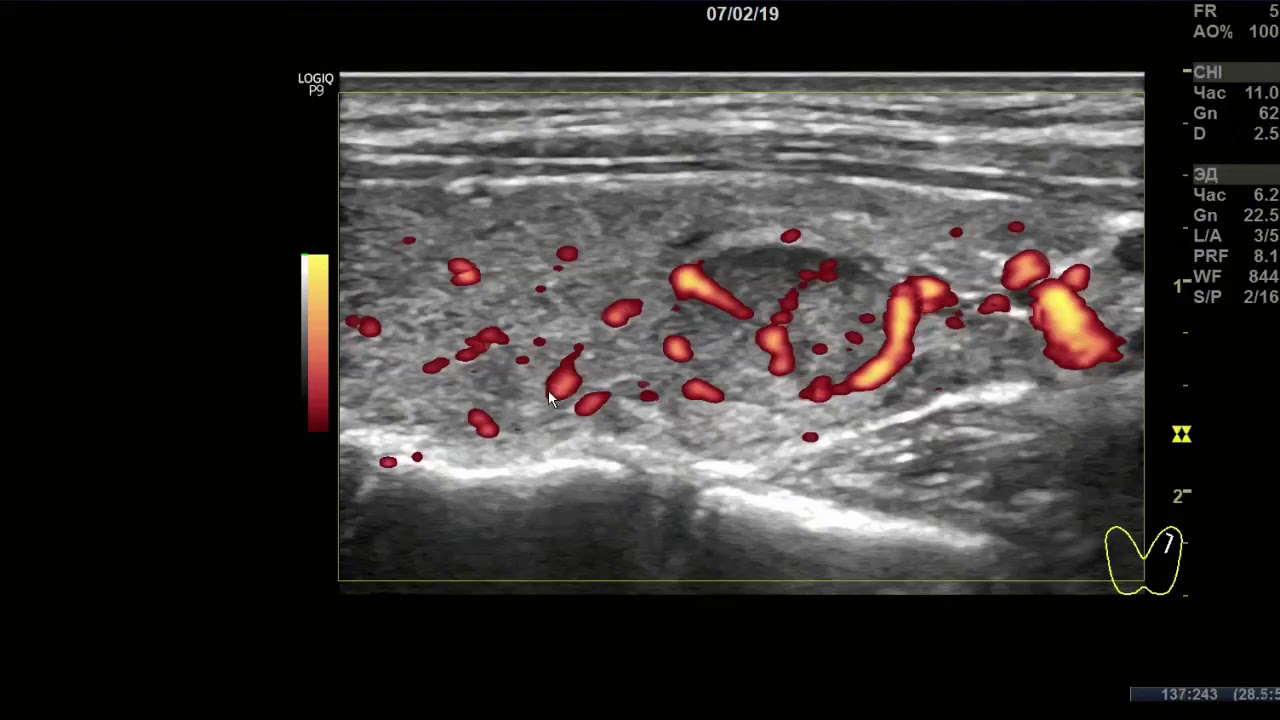

Допплер-УЗИ – это вид анализа, который позволяет совместить черно-белое изображение щитовидной железы с цветным отображением кровяного тока. Оно позволяет определить:

- Проходимость кровеносных сосудов

- Нарушения их стенок (утончение/утолщение)

- Направление и скорость

- Индекс сопротивления

УЗИ признаки рака щитовидной железы можно дополнить, если применить допплеровское исследование во время процедуры.

Это позволяет утвердить подозрения насчет онкологического процесса, так как датчик допплера покажет значительное усиление кровоснабжения пострадавшей зоны.

В ходе ультразвуковой диагностики щитовидки для исследования особенностей кровотока в тканях органа используется метод допплеровского сканирования — цветное картирование (ЦДК). Это новейшая методика, позволяющая совместить простое черно-белое изображение на экране монитора с цветовыми обозначениями тока крови (красным и синим). Процедура ЦДК обязательна при некоторых заболеваниях щитовидки.

Считается, что метод ЦДК является весьма информативным, поскольку с помощью него в заключение УЗИ щитовидной железы могут быть внесены такие важные показатели, как:

- направление и скорость кровотока;

- индекс резистентности и сопротивления;

- степень проходимости и извитости сосудов, их диаметр;

- утолщение/истончение сосудистых стенок.

Если путем ЦДК обнаружили значительные нарушение кровотока, то вероятность рака увеличивается. Кроме того, о возможном раке говорят тогда, когда ткань образования выглядит как темное пятно без четких границ.

Кровообращение в железе может как увеличиваться, так и снижаться. Снижение в большинстве случаев приводит к опасным осложнениям, таким как атрофирование тканей. Нормальные показатели кровотока выражены на мониторе как разноцветные равно распределенные сигналы по всей железе.

Увеличение кровотока (изображение справа) при злокачественном процессе

Воспалительные процессы приводят к усилению кровообращения в органе. На мониторе при проведении допплерографии с ЦДК (цветным доплеровским картированием) это выглядит в виде своеобразного огня, расположенном в каком-либо определенном участке. Нормой считается равномерное стабильное цветовое окрашивание. При УЗИ щитовидки с ЦДК учитываются следующие характеристики кровотока:

- направленность и скорость;

- индекс сопротивления и резистентности;

- истончение или утолщение сосудистых стенок;

- диаметр сосудов, их извитость и степень проходимости.

Выявление значительных нарушений кровообращения в отдельном участке щитовидной железы зачастую является свидетельством образования и развития онкологического процесса злокачественного характера.